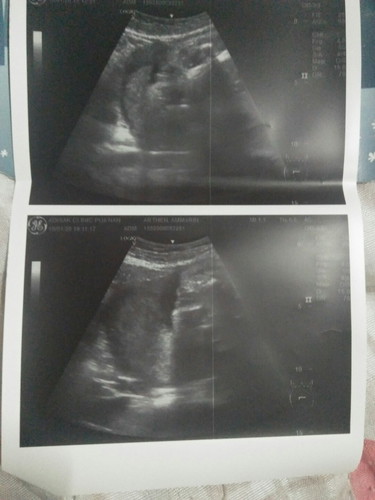

สอบถามคุณแม่เรื่องเพศ

ไม่ทราบว่าชายหรือหญิงค่ะ

ไม่ชัดค่ะ มองไม่เห็น

ภาพไม่ชัดเลยจ้า